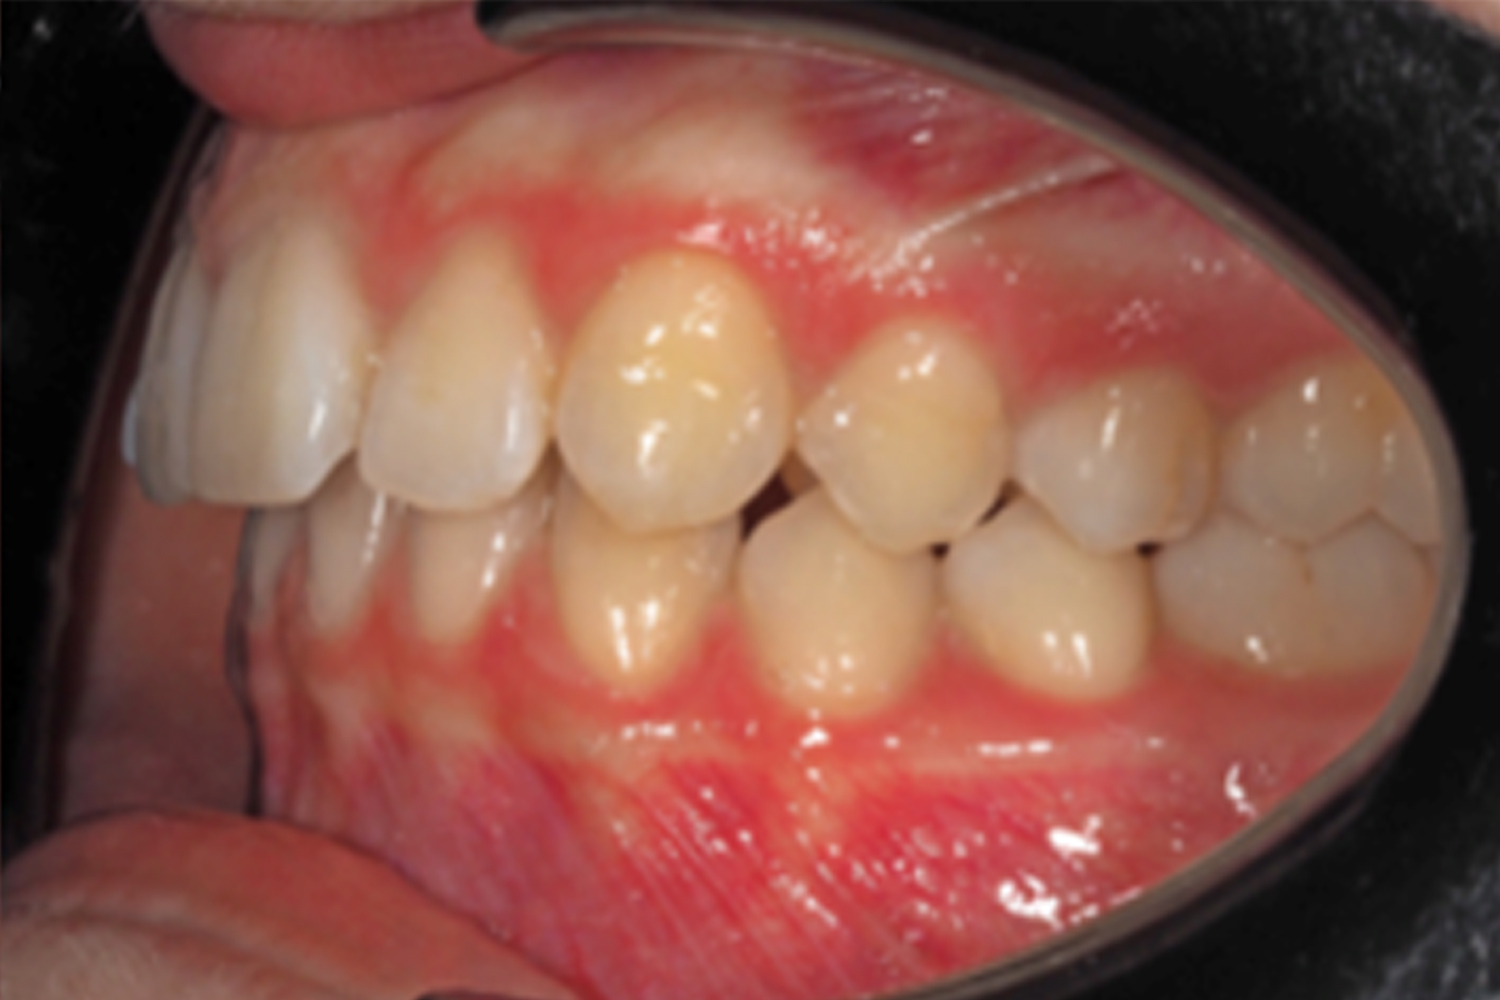

The 17-year-old female patient, who had previously undergone an orthodontic treatment 4 years ago, came to the dental clinic in May 2022. She was concerned about her upper right lateral incisor tipping, which was worsening over time, making her feel uncomfortable while smiling.

The extraoral examination revealed isometric contraction of the left side muscles, mild canted maxillary occlusal plane, facial and upper midlines centered and hypodivergent facial pattern.

During intraoral examination the patient was found to have: